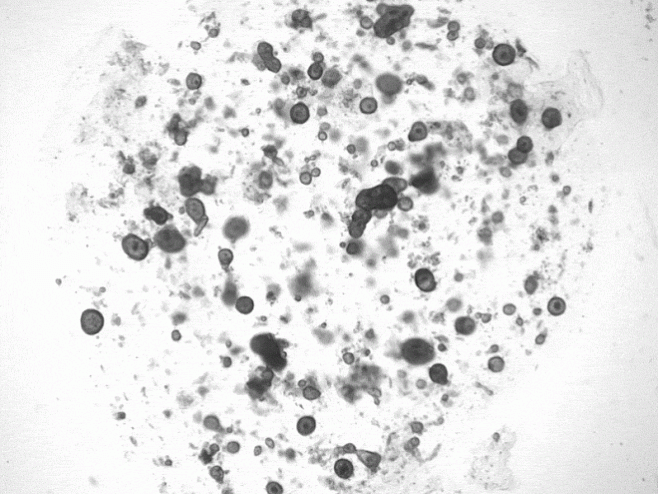

Слезные железы расположены над каждым глазным яблоком, и проведение их биопсии – задача непростая: даже если исследователям удается взять образцы для анализа, они, как правило, очень крохотные. Поэтому специалисты из Утрехта пошли другим путем: они создали условия для выращивая клеточных культур из клеток слезных желез человека и мышей, а для стимуляции выработки слезной жидкости подвергли органеллы воздействию нескольких химических веществ, включая норэпинефрин – нейромедиатор, который передает «послания» от нейронов к железам. Поскольку у органелл нет протоков, выработка «слез» заставила их разбухнуть (при наличии протоков образовались бы капли). Когда исследователи пересадили органеллы мышам, клетки смогли сформировать похожие на протоки структуры, которые содержали характерные для слез белки.

Фото: Marie Bannier-Hélaouët/Hubrecht Institute